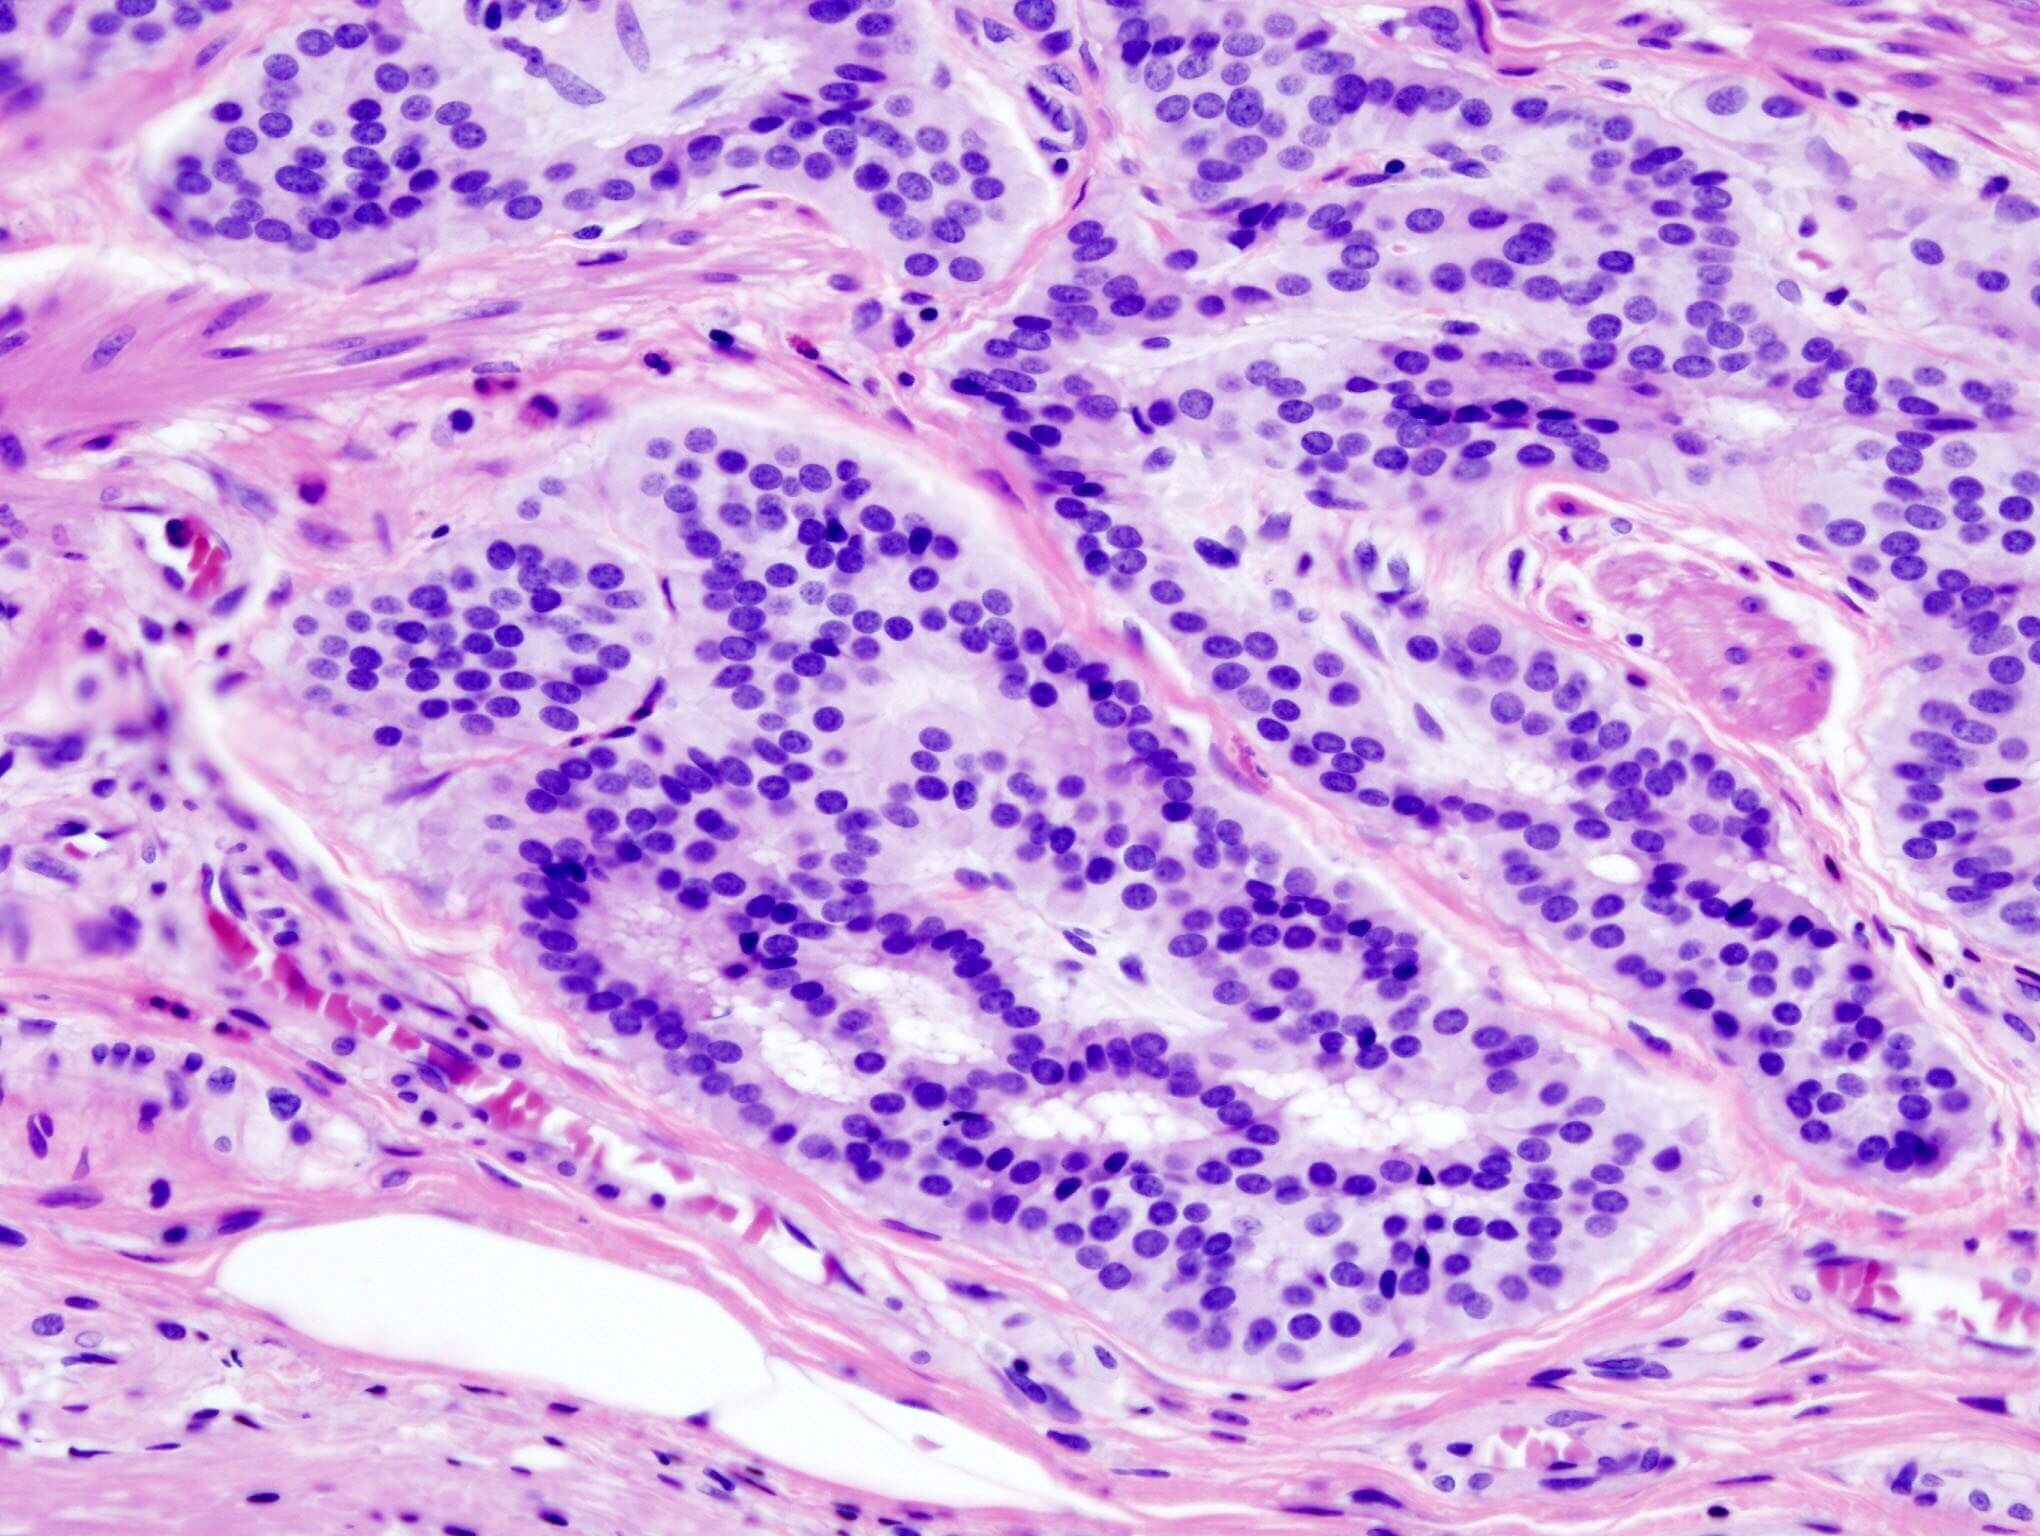

La nuova terapia, denominata Kymriah (tisagenlecleucel), potrà essere prescritta secondo le indicazioni approvate da EMA e utilizzata presso i centri specialistici selezionati dalle Regioni, per pazienti adulti con linfoma diffuso a grandi cellule B (DLBCL) resistenti alle altre terapie o nei quali la malattia sia ricomparsa dopo una risposta ai trattamenti standard e per pazienti fino a 25 anni di età con leucemia linfoblastica acuta (LLA) a cellule B.

Le terapie CAR-T rappresentano una strategia immunoterapica di ultimissima generazione nella lotta ai tumori ematologici. Utilizzano i globuli bianchi (linfociti T) prelevati dal paziente e appositamente ingegnerizzati per attivare il sistema immunitario; una volta reinfusi nel paziente, entrano nel circolo sanguigno e sono in grado di riconoscere le cellule tumorali e di eliminarle.